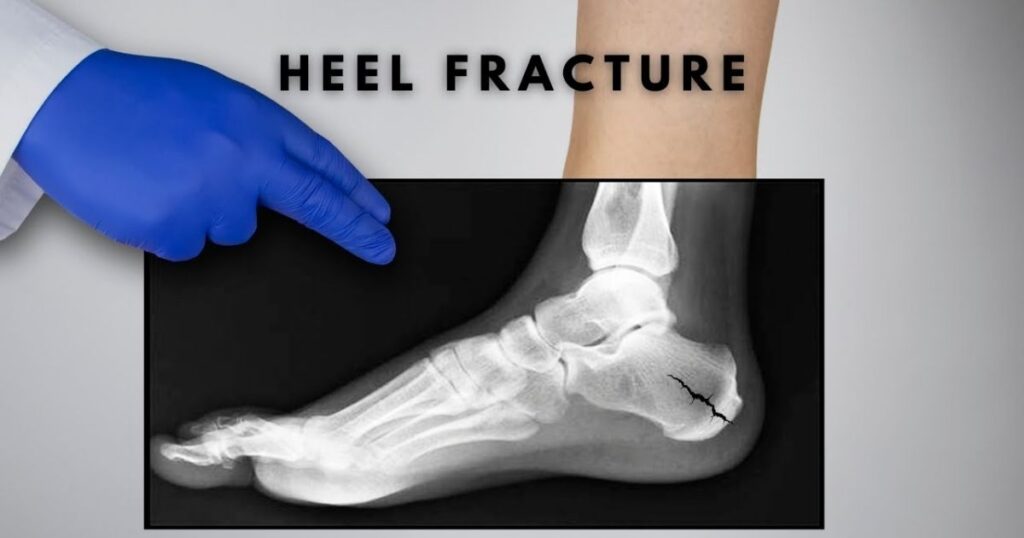

Heel Stress Fractures (Calcaneal)

Calcaneal fractures affect the heel bone. They’re less common in runners but show up more frequently in military trainees and people who’ve recently started high-impact exercise after a long sedentary period. The pain is typically a stabbing heel pain that’s worst first thing in the morning or when resuming activity after rest, which makes it easy to confuse with plantar fasciitis.

One distinction: plantar fasciitis pain tends to ease as you walk and warm up. Heel stress fracture pain often persists or worsens with continued activity.